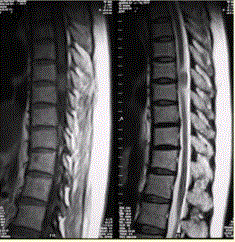

问题 患者女,52岁,颈部不适2年。MRI检查结果如下图。 关于脊膜瘤,正确的是

选项 A.好发于女性 B.有完整包膜 C.瘤体内可见钙化 D.发病率占髓外硬膜下肿瘤的第2位 E.可以跨硬膜生长 F.均匀中等至明显强化

答案 ABCDEF